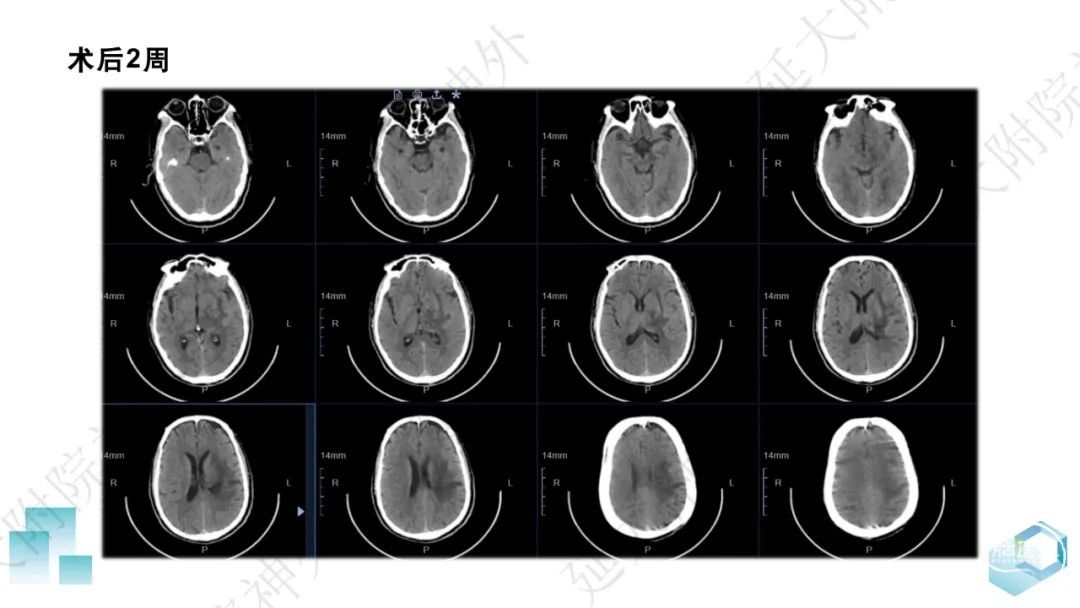

今天为大家分享的是《监测有道丨颅脑创伤-神经重症周刊》第332期,由延安大学附属医院神经外科贾云峰主任医师带来的:左侧基底节区出血破入脑室一例神经内镜下血肿清除术,欢迎阅读、分享。

长期从事神经外科疾病的基础与临床研究。专长于神经急危重症综合治疗、神经内镜脑出血微创手术、脊髓脊柱疾病显微外科微创治疗、颅内及脊髓肿瘤、脑血管病、脑、脊髓先天畸形的微创治疗。参与主持完成科研项目《尼莫地平对脊髓损伤的作用研究》等,获陕西省自然科学优秀论文奖。参与国家卫健委牵头的《自发性脑出血的多中心登记研究》等项目研究及《脑出血患者颅内压监测》《脑出血后脑水肿的治疗》专家共识的制定。以第一作者在国内外发表核心期刊20余篇,SCI收录文章1篇,多次应邀在中华医学会、中国医师协会全国神经外科学年会交流发言。主编及参编著作3部,国家发明专利2项